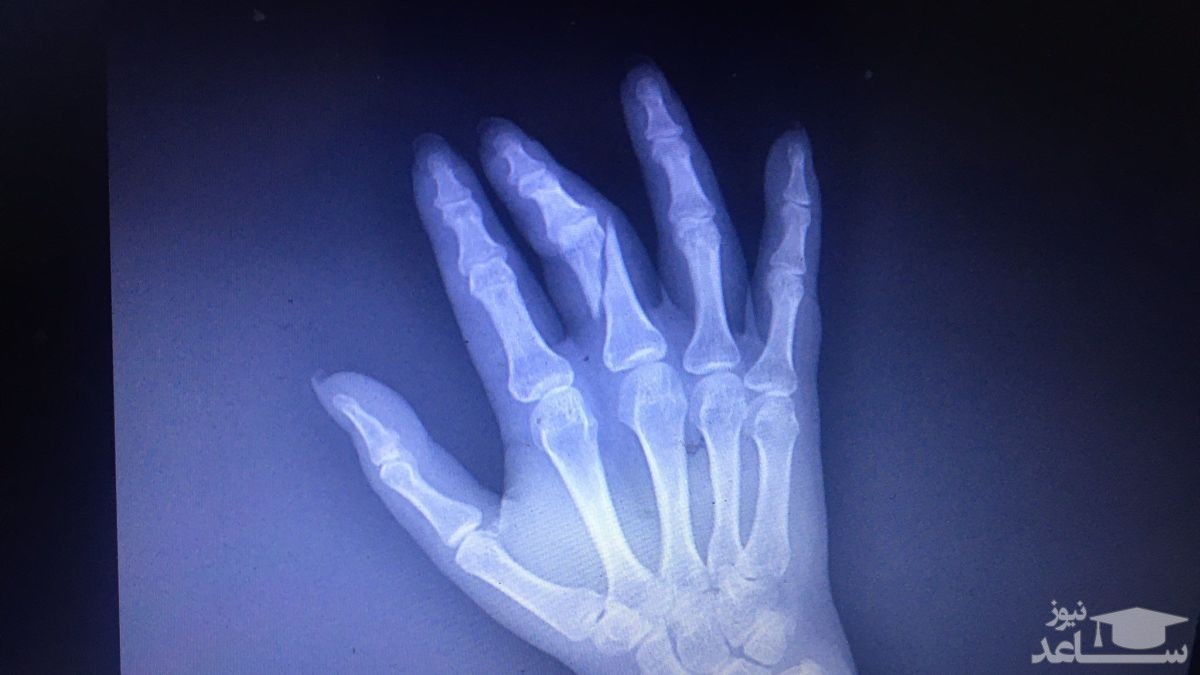

(فیلم) ماجرای شکستن دست خبرنگار توسط حراست دانشگاه شهید بهشتی

ساعد نیوز: دست یک خبرنگار به دلیل تهیه گزارش از نحوه واکسیناسیون عمومی شکسته شد. این خبرنگار در گفتگو با شبکه خبر در مورد اتفاق توضیح داد.